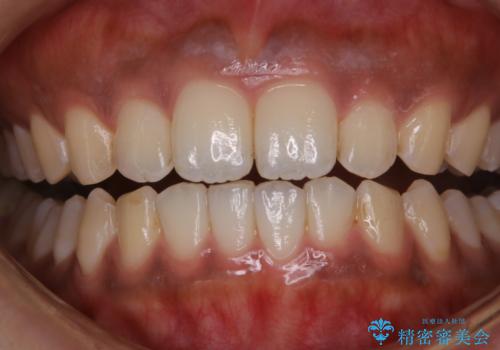

タバコのステインを徹底的に除去

- タバコによるステインを綺麗にしたいとのことでした。

PMTC60分コースを行いました。

PMTCでは、歯の表面の凸凹にミネラルを補給して、ツルツルの表面に仕上げます。定期的にPMTCを行うことにより、歯質の強化になり着色がつきにくい状態になります。